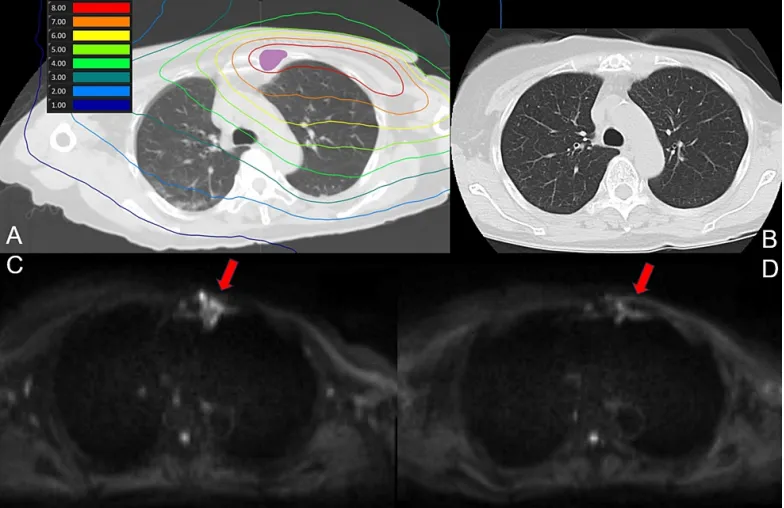

該患者在BNCT治療前有12年以上的左側(cè)乳腺癌化療史,隨后進(jìn)行了乳房切除,后左側(cè)胸骨旁淋巴結(jié)復(fù)發(fā),接受了激素治療和化療。4年前,該患者接受了左側(cè)胸壁和胸骨旁區(qū)域的放射治療,共30次,總劑量為59Gy,盡管此區(qū)域治療后未再復(fù)發(fā),但左側(cè)乳腺內(nèi)淋巴結(jié)出現(xiàn)復(fù)發(fā),遂開始BNCT治療。腫瘤靶區(qū)(GTV) 的最小處方劑量為31.4Gy-Eq,同側(cè)肺的平均劑量為5Gy-Eq。在BNCT治療后第1和第7天對(duì)患者進(jìn)行了MRI檢查,第30和90天進(jìn)行了CT檢查,均未發(fā)現(xiàn)放射性肺炎跡象。圖1顯示了肺部區(qū)域的劑量分布以及治療后90天的CT和MRI掃描結(jié)果。

(A) BNCT(肺)劑量分布圖。紫色代表腫瘤總體積

(B) 治療90天后CT掃描未見放射性肺炎征象

(C) 治療前彌散加權(quán)成像MRI

(D) MRI掃描90天顯示信號(hào)強(qiáng)度降低